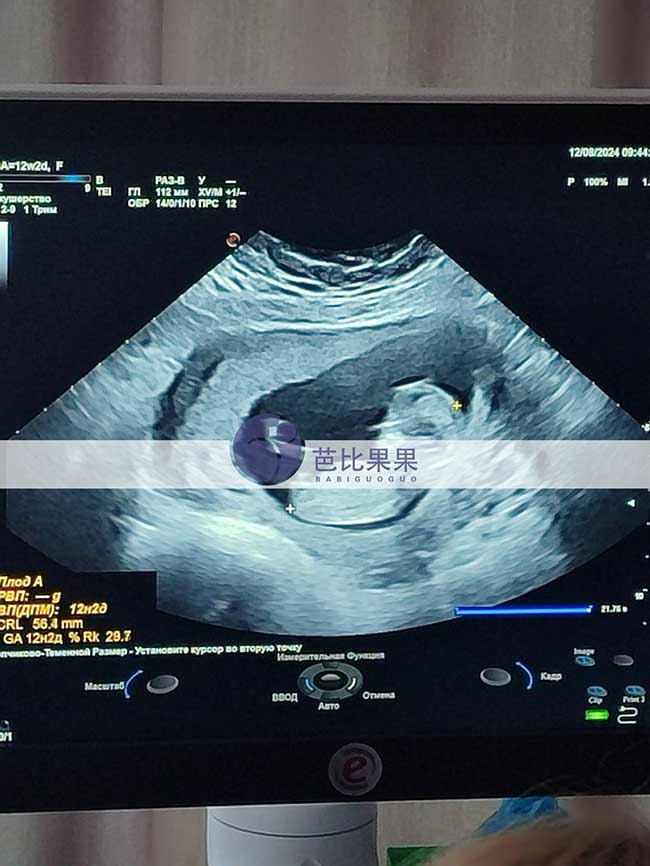

C女士在乌克兰DY匹配的试管妈妈来做孕12周的B超

C女士在乌克兰DY匹配的试管妈妈来做孕12周的B超啦,试管妈妈美美的,双胞胎宝宝也发育的很好